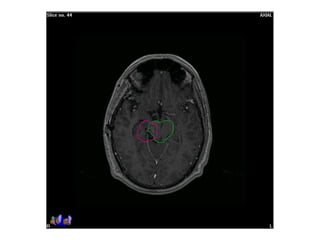

RT planning: meningioma

GTV/CTV = residual tumour / tumour bed for gr II / gr III

CTV = 5 mm for benign meningiomas

2 - 3 cms for high grade meningiomas / HPC

PTV = 2mm for SRT

5mm for 3DCRT

All normal structures contoured

Dosage:

Gr-I:

54Gy/30# conformal RT

25Gy/5# / 13Gy/1#

Gr II & III meningioma:

60Gy/30#/6wks

Conformal RT

Grade I Grade II/III

Tharmoplastic mask

CT scan with contrast- 3 mm slice

MRI scan with T1 contrast & T2 flair is a must